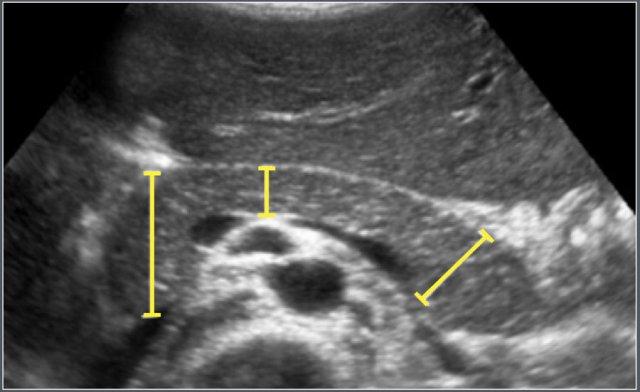

Tụy

Vật liệu và Phương pháp

Nghiên cứu siêu âm hồi cứu này bao gồm 273 bệnh nhân nhi (phân bố giới tính không được ghi rõ).

Đường kính trước-sau (AP) lớn nhất của đầu, thân và đuôi tụy được đo trên các mặt cắt siêu âm ngang hoặc chếch.